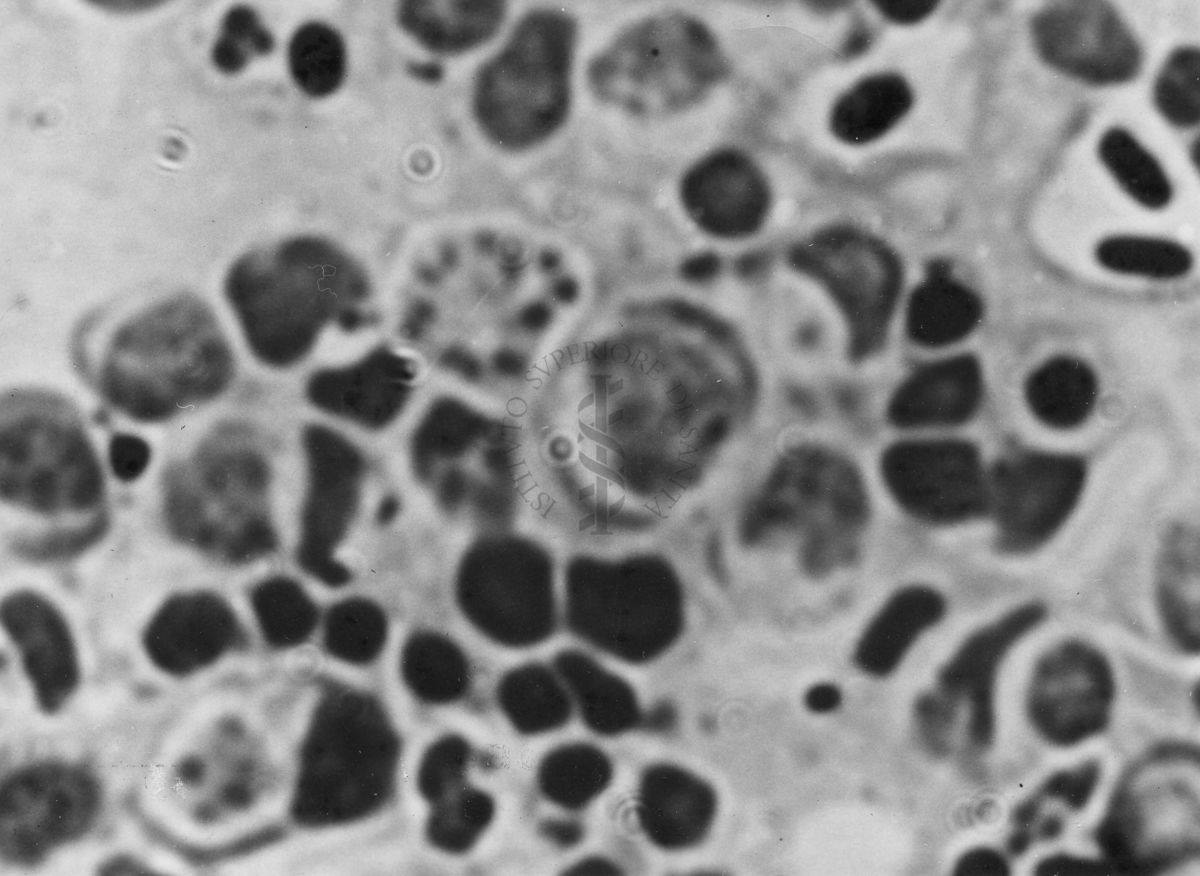

Immagini di Emoprotozoi